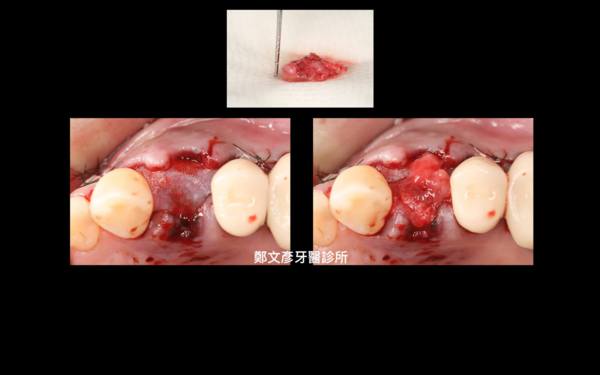

Role of granulation tissue in socket preservation

3. Role of granulation tissue in socket preservation